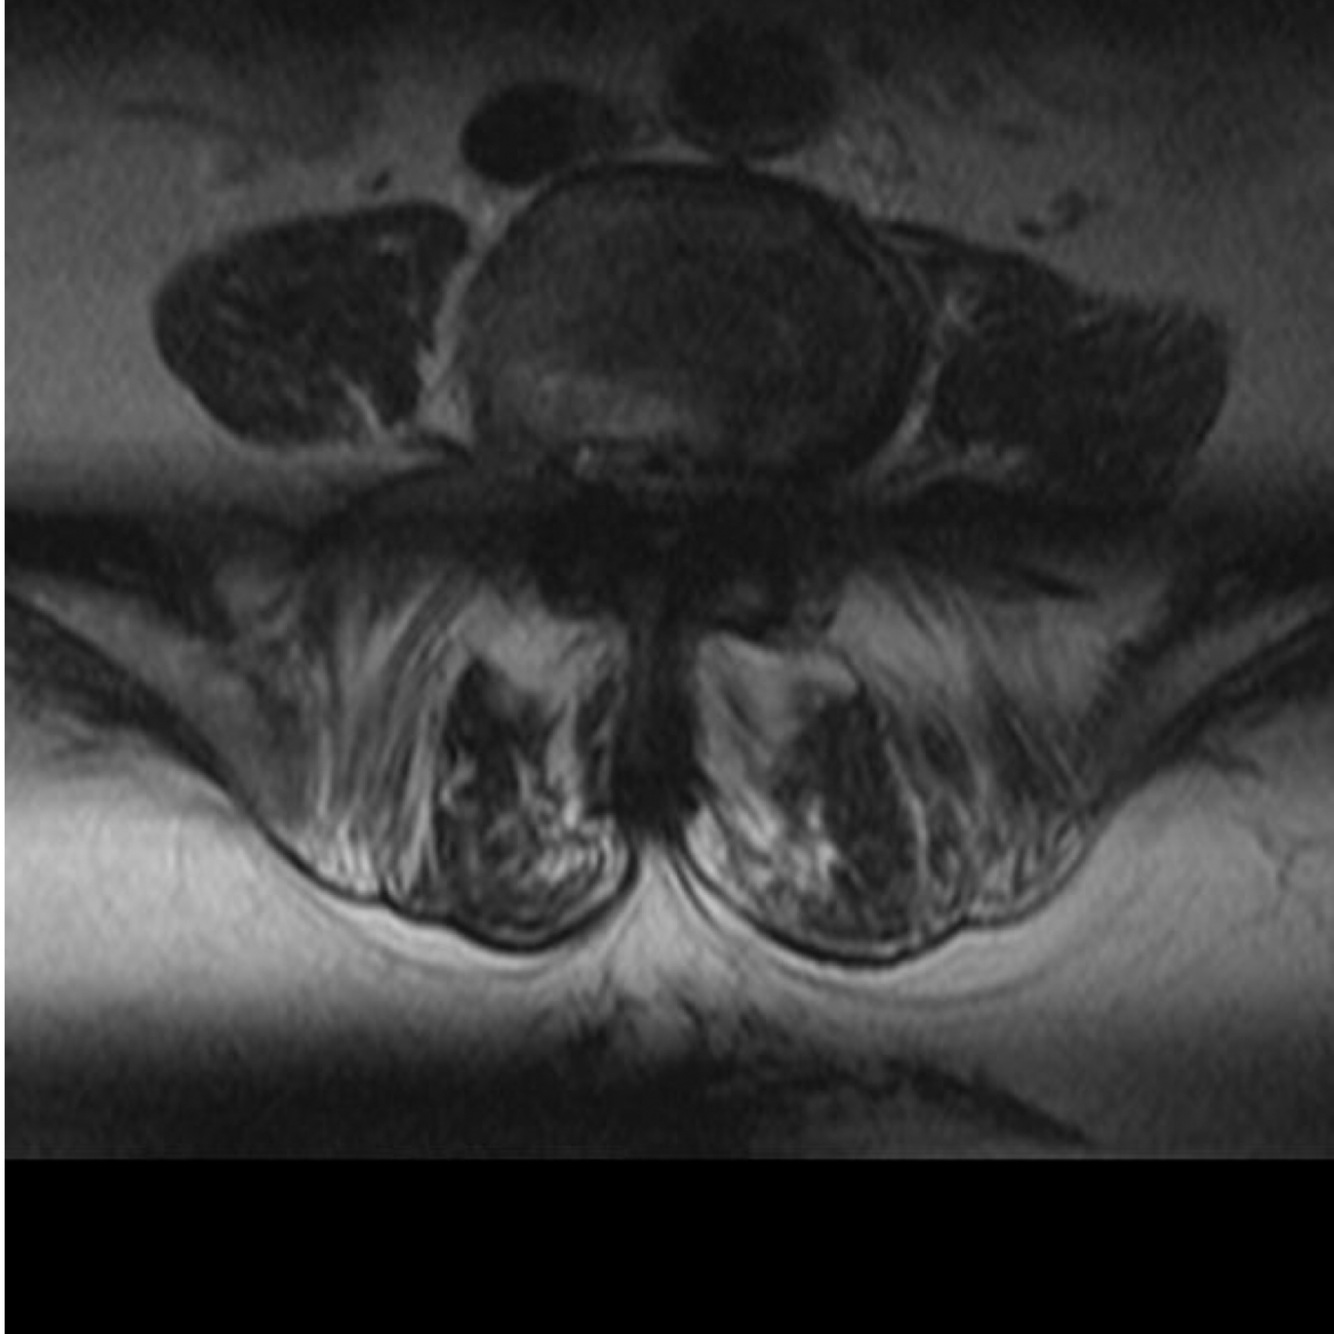

The slice-overlap artifact, also known as cross-talk artifact, is a type of MRI artifact, namely, the loss of signal seen in an image from a multi-angle, multi-slice acquisition, as is obtained commonly in the lumbar spine. It should not be confused with cross excitation which although similar in causation, is not due to angled images. If the slices obtained at different disk spaces are not parallel, they may overlap. If two levels are acquired at the same time, e.g. L4-L5 and L5-S1, the level acquired second will include spins that have already been saturated. This causes a horizontal band of signal loss crossing the image, usually most pronounced posteriorly. The dark horizontal band at the bottom of the following axial image through the lumbar spine demonstrates this artifact.